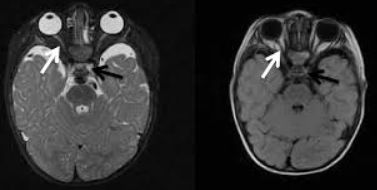

Visual acuity and visual field tests are a good screen to test for chiasmal involvement. Neuroimaging may also be needed (i.e. MRI (magnetic resonance imaging)). In some cases, endocrinologic evaluation should be considered when the cause is pituitary adenoma, which is the most common extrinsic cause of chiasmal syndrome. A pattern electroretinogram may be measured to predict the visual prognosis of patients with chiasmal compression.